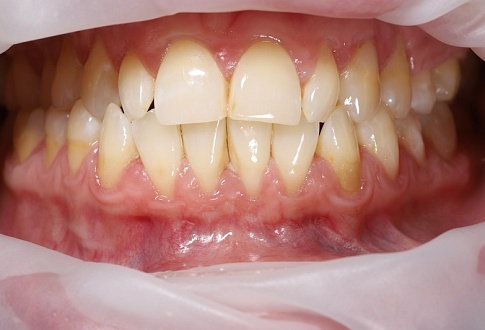

Наращивание десны

Фото «До» и «После»

Внимание! Изображение может вызвать шок или неприятные эмоции.